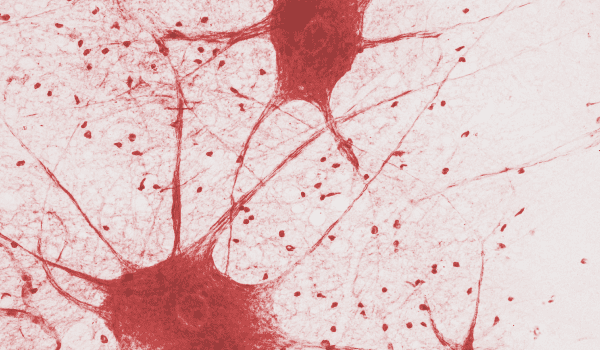

Нейрон 一 основная структурная единица нервной ткани. Это возбудимая клетка, которая может генерировать и проводить нервный импульс2. Благодаря контактам между множеством нейронов в мозге возможна привычная нам нервная деятельность2.

В исследовании 2021 года ученые смогли составить атлас части мозга размером всего в 1 кубический миллиметр. Оказалось, что в нем находится 50 000 нервных клеток с 130 миллионами связей между ними. Все собранные данные заняли объем более 1 петабайта памяти3. Для сравнения: весь Youtube весит около 5 петабайтов 4. А в среднем в мозге насчитывается около 86 миллиардов нейронов и около 1 200 000 кубических миллиметров объема5. Простые подсчеты говорят нам, что, чтобы приблизиться к расшифровке мозговой деятельности, нужно более миллиона петабайтов памяти. Эта огромная цифра сравнима с объемом всего мирового интернет-трафика в 2016 году4.

Мысли способны менять структуру и функции нашего мозга. Он меняется под воздействием жизненного опыта человека: какие-то контакты между нейронами укрепляются, а какие-то разрушаются. Когда человек получает новое знание или сталкивается с новым опытом, в мозге закрепляются серии устойчивых нейронных связей6. По ним нейроны могут обмениваться между собой информацией. Чем чаще человек пользуется полученным опытом, тем крепче становятся связи, и, наоборот, долго невостребованные связи постепенно ослабляются6